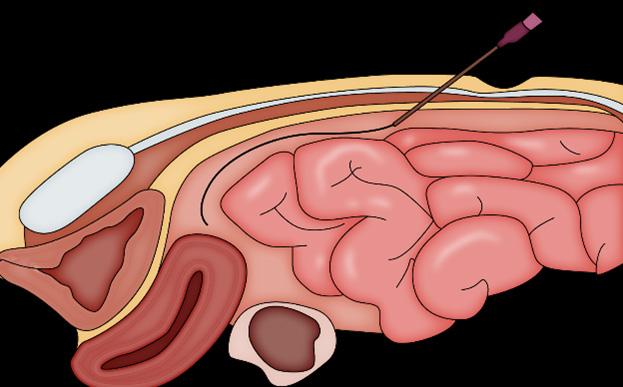

LPD (Lavado peritoneal diagnóstico): estudio más específico pero invasivo (ENARM 2015, ENARM 2018). Es positivo si: 10 ml de aspirado sanguíneo inicial > 100.000 eritrocitos o > 500 leucocitos por mm3

Si el examen FAST no está disponible, se debe llevar a un paciente hemodinámicamente inestable al quirófano de inmediato.